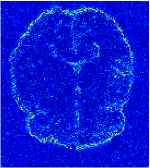

All the experiments are implemented on a Windows workstation with Intel Core i9 CPU at 3.3GHz and an Nvidia GTX-1080Ti GPU with 11GB of graphics card memory via TensorFlow Abadi et al. (2016). The parameters in the proposed network are initialized by using Xavier initialization Glorot and Bengio (2010). We trained the meta-learning network with four tasks synergistically associated with four different CS ratios: 10%, 20%, 30%, and 40%, and test the well-trained model on the testing dataset with the same masks of these four ratios. We have 300 training data for each CS ratio, which amount to total of 1200 images in the training dataset. The results for and MR reconstructions are shown in Tables 5.4 and 5.4 respectively. The associated reconstructed images are displayed in Figures 1 and 3. We also test the well-trained meta-learning model on unseen tasks with radio masks for skewed ratios: 15%, 25%, 35%, and random Cartesian masks with ratios 10%, 20%, 30% and 40%. The task-specific parameter for the unseen tasks are retrained for different masks with different sampling ratios individually with fixed task-invariant parameters . In this experiments, we only need to learn for three skewed CS ratios with radio mask and four regular CS ratios with Cartesian masks. The experimental training proceed on less data and iterations, where we performed on 100 MR images with 50 epochs. For example, for reconstructing MR images with CS ratio 15% radio mask, we fix the parameter and retrain the task-specific parameter on 100 raw data with 50 epochs, then test with renewed on our testing data set with raw measurement that sampled from radio mask with CS ratio 15%. The results associated with radio masks are shown in Table 5.4 and 5.4, Figure 2 and 4 for and images respectively. The results associated with Cartesian masks are list in Table 5.4 and reconstructed images are displayed in Figure 5.

Qualitative comparison between conventional and Meta-learning methods are shown in Figure 1 and 3, which display the reconstructed MR images of the same slice for T1 and T2 respectively, we label the zoomed-in details of HGG in the red boxes. We observe the evidence that conventional learning is more blurry and lost sharp edges, especially in lower CS ratios. From the point-wise error map, we find meta-learning has the ability to reduce noises especially in some detailed and complicated regions comparing to conventional learning.